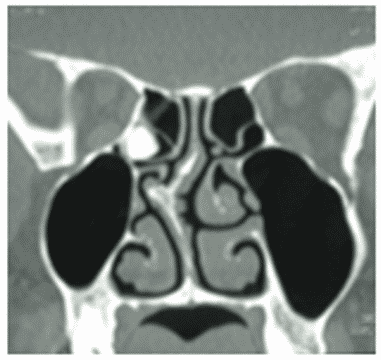

Остеома - КТ позволяет не только выявить наличие остеомы околоносовых пазух, но и определить тип ее строения, установить место исходного роста. Рентгеновская картина остеомы соответствует ее строению. Компактные остеомы - шаровидные, округлые опухоли, имеющие вид плотного, почти бесструктурного новообразования (рисунок 1).

Рис. 1. КТ околоносовых пазух, коронарная (А) и аксиальная (Б) плоскости: Компактная остеома решетчатого лабиринта справа в виде округлого добавочного интенсивного образования с четкими ровными контурами